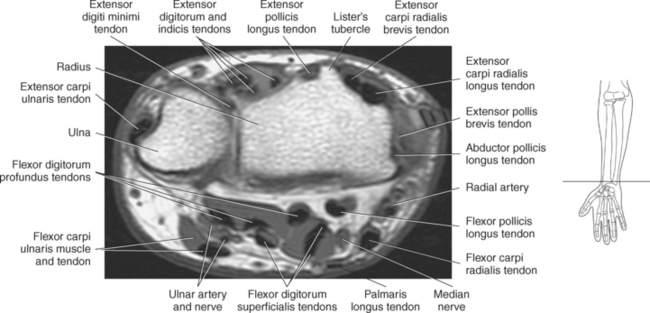

Figure 9.119 Axial, T1-weighted MR scan of wrist with flexor and extensor tendons.

Key: ex, Extensor tendons; c, capitate; h, hamate; fl, flexor tendons; flr, flexor retinaculum; mn, median nerve; tm, trapezium; td, trapezoid.